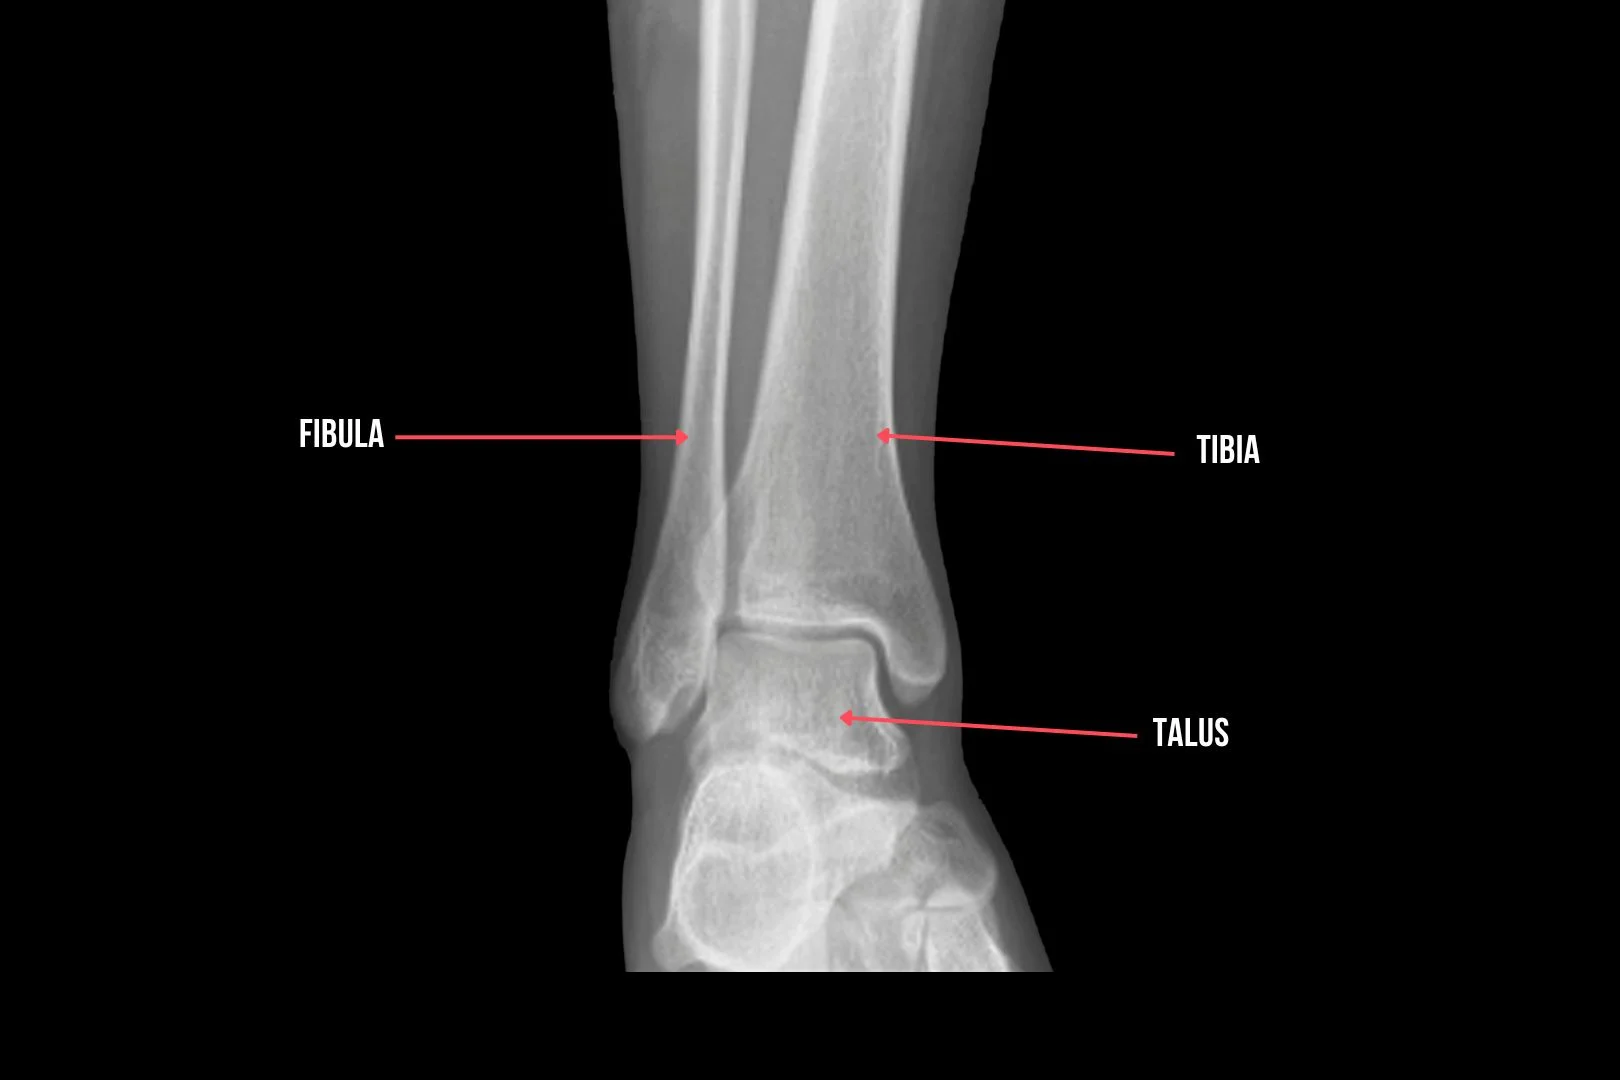

Bones

Imagine your ankle as a bridge between your leg and foot. The main bones involved are the tibia (shinbone), fibula (calf bone), and talus (ankle bone). Together, they form a sturdy structure that allows you to walk, run, and jump with ease. They are the foundation of the anatomy of the ankle.